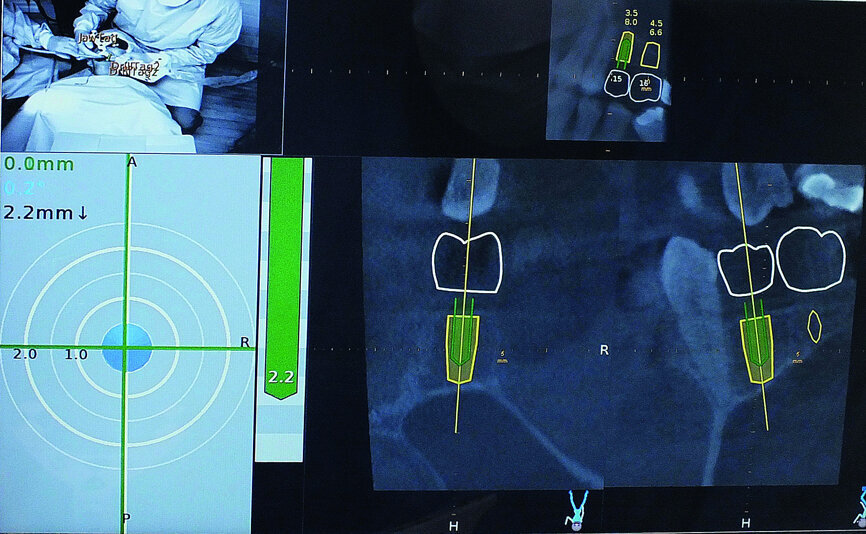

Fig. 7: The pathway of the drill could be followed clearly on the Navident computer screen.

Fig. 8: Navident provided visual confirmation of the position of the drill tip to accurately gauge the correct depth.

The scan was taken with a Morita 3-D CBCT system, which provides high definition, distortion-free images for accurate diagnosis and planning. Radiographic and CBCT examination revealed approximately 9 mm of bone depth, from the crest of the ridge to the floor of the maxillary antrum, in the upper right second premolar site, and no more than 5 mm bone depth in the first molar site. Planning took place immediately after the scan, with the patient present, so she could see the proposed treatment on the Navident software. She felt reassured by the care being taken to achieve optimum implant positioning, with minimal risk of potential complications, and was extremely impressed with the technology.

The Navident planning software allowed the placement of the implants to be restoratively driven. The size, shape and position of the intended crowns were planned prior to treatment and the consequent position of the implants determined, so that the optimum restoration could be achieved.

Navident was used to guide the implant site preparation dynamically, to ensure implants were placed in the pre-determined position without the need for a static drilling guide. This facilitated placement of the implants in the optimum amount of bone without inadvertent damage to the maxillary sinus membrane. It also ensured that their alignment made future impression taking and restoration straightforward. The ability to watch the drill virtually on the CBCT scan, as the implant sites were prepared, allowed the exact point at which to cease vertical drilling to be judged visually.